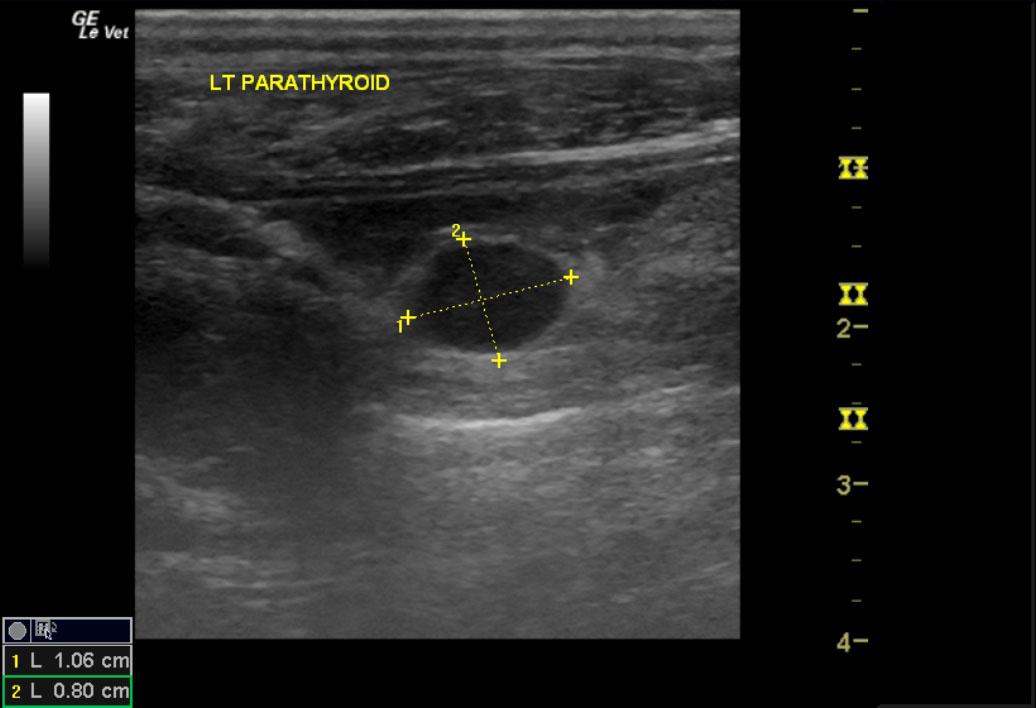

A 10-year-old M Beagle was referred for ultrasonography after presenting for history of hypercalcemia, elevated cholesterol, and dysuria. A parathyroid panel was within normal limits.